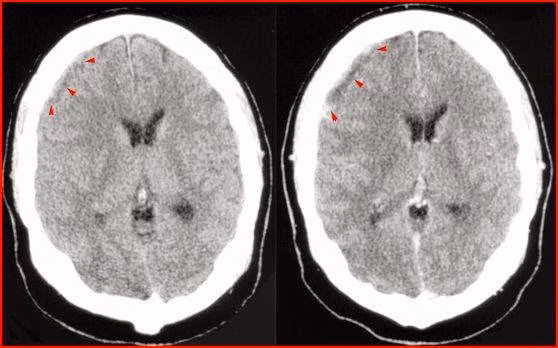

Tràn dịch dưới màng cứng. Hay gặp ở trẻ nhỏ và bú mẹ, đặc biệt trong trường hợp H.influenzae và phế cầu. Nghi ngờ khi sốt kéo dài, tái phát, ngủ lịm, hôn mê, co giật khu trú, vòng đầu tăng. Chẩn đoán nhờ siêu âm và scanner.